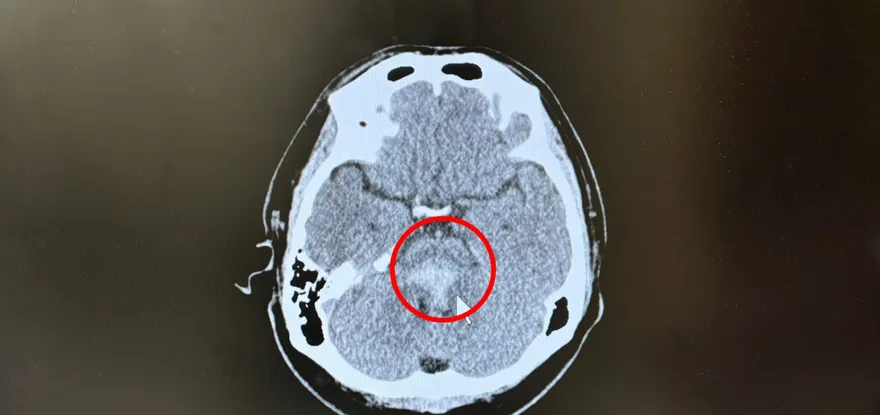

腦傷

瞳孔放大

電腦斷層

奇美醫院

低溫療法